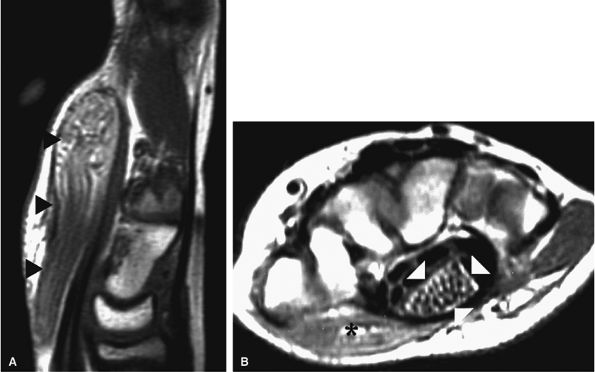

![]() |

FIGURE 12.20 ● Ulnar neurop-athy secondary to scar. Axial T1-weighted (A) and fat-suppressed T2-weighted (B) images demonstrate encasement of the ulnar nerve (arrowhead) by scar tissue (arrows). Selective denervation edema of the flexor carpi ulnaris (fcu) muscle in the proximal forearm is noted.

Selective denervation edema and atrophy of the flexor carpi ulnaris and flexor digitorum profundus muscles, best appreciated on axial forearm images, are additional contributory features in the MR diagnosis of ulnar neuropathy (see Fig. 12.20).62